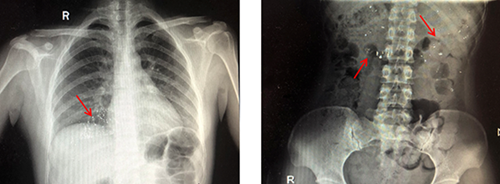

幾天前, 2歲的芯芯(化名)在家量完體溫后,趁媽媽不注意,將體溫計咬破,并將水銀和一部分玻璃碎屑吞掉。孩子爸爸媽媽嚇壞了,立刻到孩子到青島婦兒醫(yī)院急診科就醫(yī)。

經(jīng)過清理口腔,洗胃,催吐,加速排泄等措施,芯芯終于將腸胃內(nèi)殘留的水銀排泄干凈。

水銀體溫計是由玻璃和金屬汞構(gòu)成,咬碎后的碎片可能會導(dǎo)致口腔、咽喉部、胃腸道黏膜的損傷,嚴(yán)重者甚至?xí)?dǎo)致穿孔。水銀經(jīng)胃腸道吸收甚微,但誤吞水銀者如果胃腸道黏膜有潰瘍傷口,水銀便會立刻進(jìn)入人體血液,危及生命安全。

除了水銀溫度計,學(xué)齡前期的孩子對外界充滿好奇心,但是沒有安全意識,硬幣、紐扣、發(fā)夾、電池、小磁鐵、棗核、小釘子等都是危險品,這些異物容易損傷消化道、氣管,甚至引起窒息等危及生命,因此,家長應(yīng)時刻看護(hù)好孩子,避開或避免接觸危險異物。一旦出現(xiàn)誤吞或誤吸異物,請及時就醫(yī)。